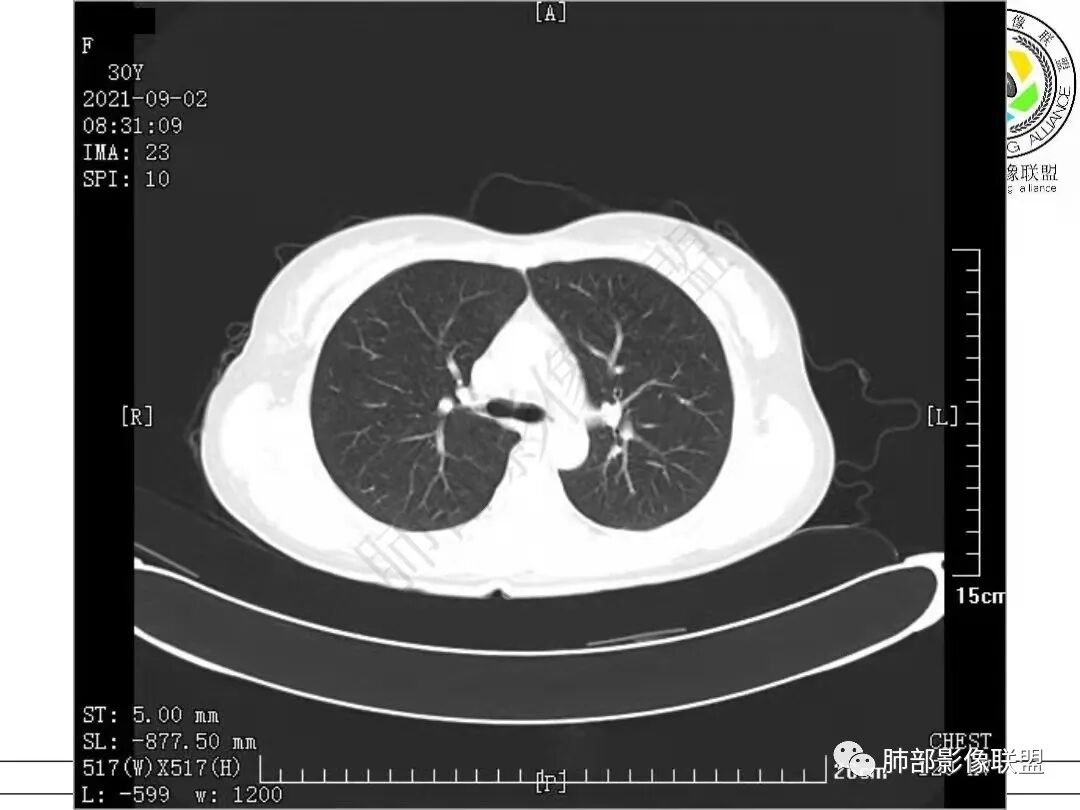

2.病例二:30岁女性,发现病灶6个月前有咳嗽咳痰及治疗史,肿瘤标志物阴性。左肺下叶胸膜下结节影,整体较膨隆,局部边缘较平直,可见毛刺,同样可见磨玻璃密度区,病灶内可见空泡征,周围可见细小毛刺及多发棘突影,同样外围病灶支气管情况难以判断。邻近肺组织内可见多发微小结节影。病灶张力不高,未见分叶及胸膜牵拉,由于纵隔窗图像太少,不宜判断胸膜下脂肪间隙有无受累,可疑胸膜下有微量积液。

综合分析:两份病例都是位于胸膜下的孤立结节,同样具有锯齿状边缘,有细毛刺、空泡。病例一老年男性+CEA显著升高,常规恶性病变肯定是要考虑;至于病例二青年女性,肿瘤标志物阴性,在未见非常典型恶性征象情况下,临床通常会优先选择炎性病灶进行处置,病灶持续存在,复查无变化或出现进展,则应想到新生物可能,而选择穿刺或其他进一步检查。